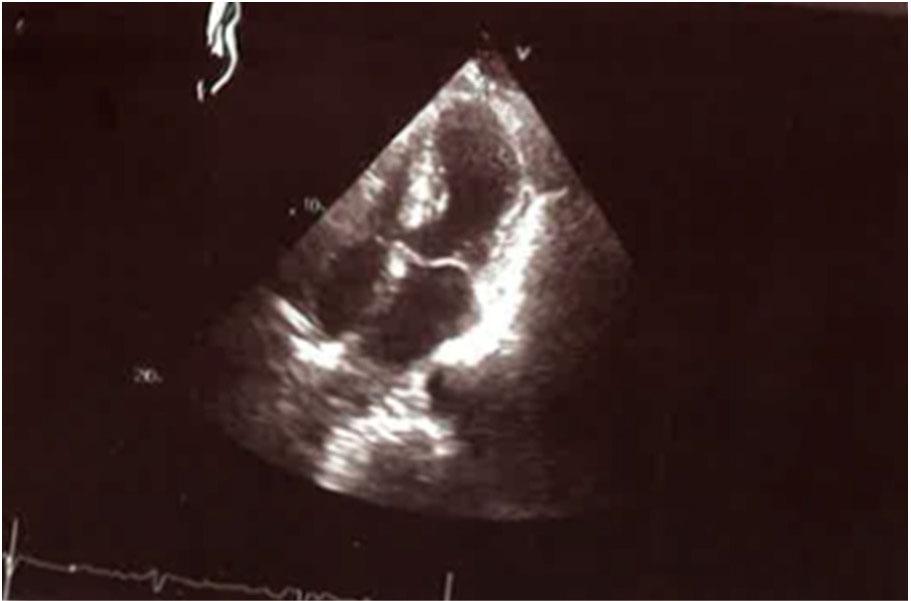

The left ventricular (LV) angiogram (Figure 1A–C) showed moderate LV systolic dysfunction with severe hypokinesis of the mid and distal anterior apical, and mid and distal inferior walls, with an ejection fraction ranging from 30% to 35%. Transthoracic echocardiographic examination performed immediately after admission shows the reference dimensions of the left ventricle, with clear systolic dysfunction of the LV, and a reduced EF of 30–35%, with clear outbursts in kinetics (hypokinesia of the anterior wall, as well as the medial and apical septum, and akinesia of the apex). An echocardiographic examination from the apex of the heart, with visualization of the 4 heart cavities, shows a ballooned apical segment of the left ventricle (Fig. 1)

Transthoracic echocardiographic apical four-chamber view in systole showing ballooning of the apical segments.